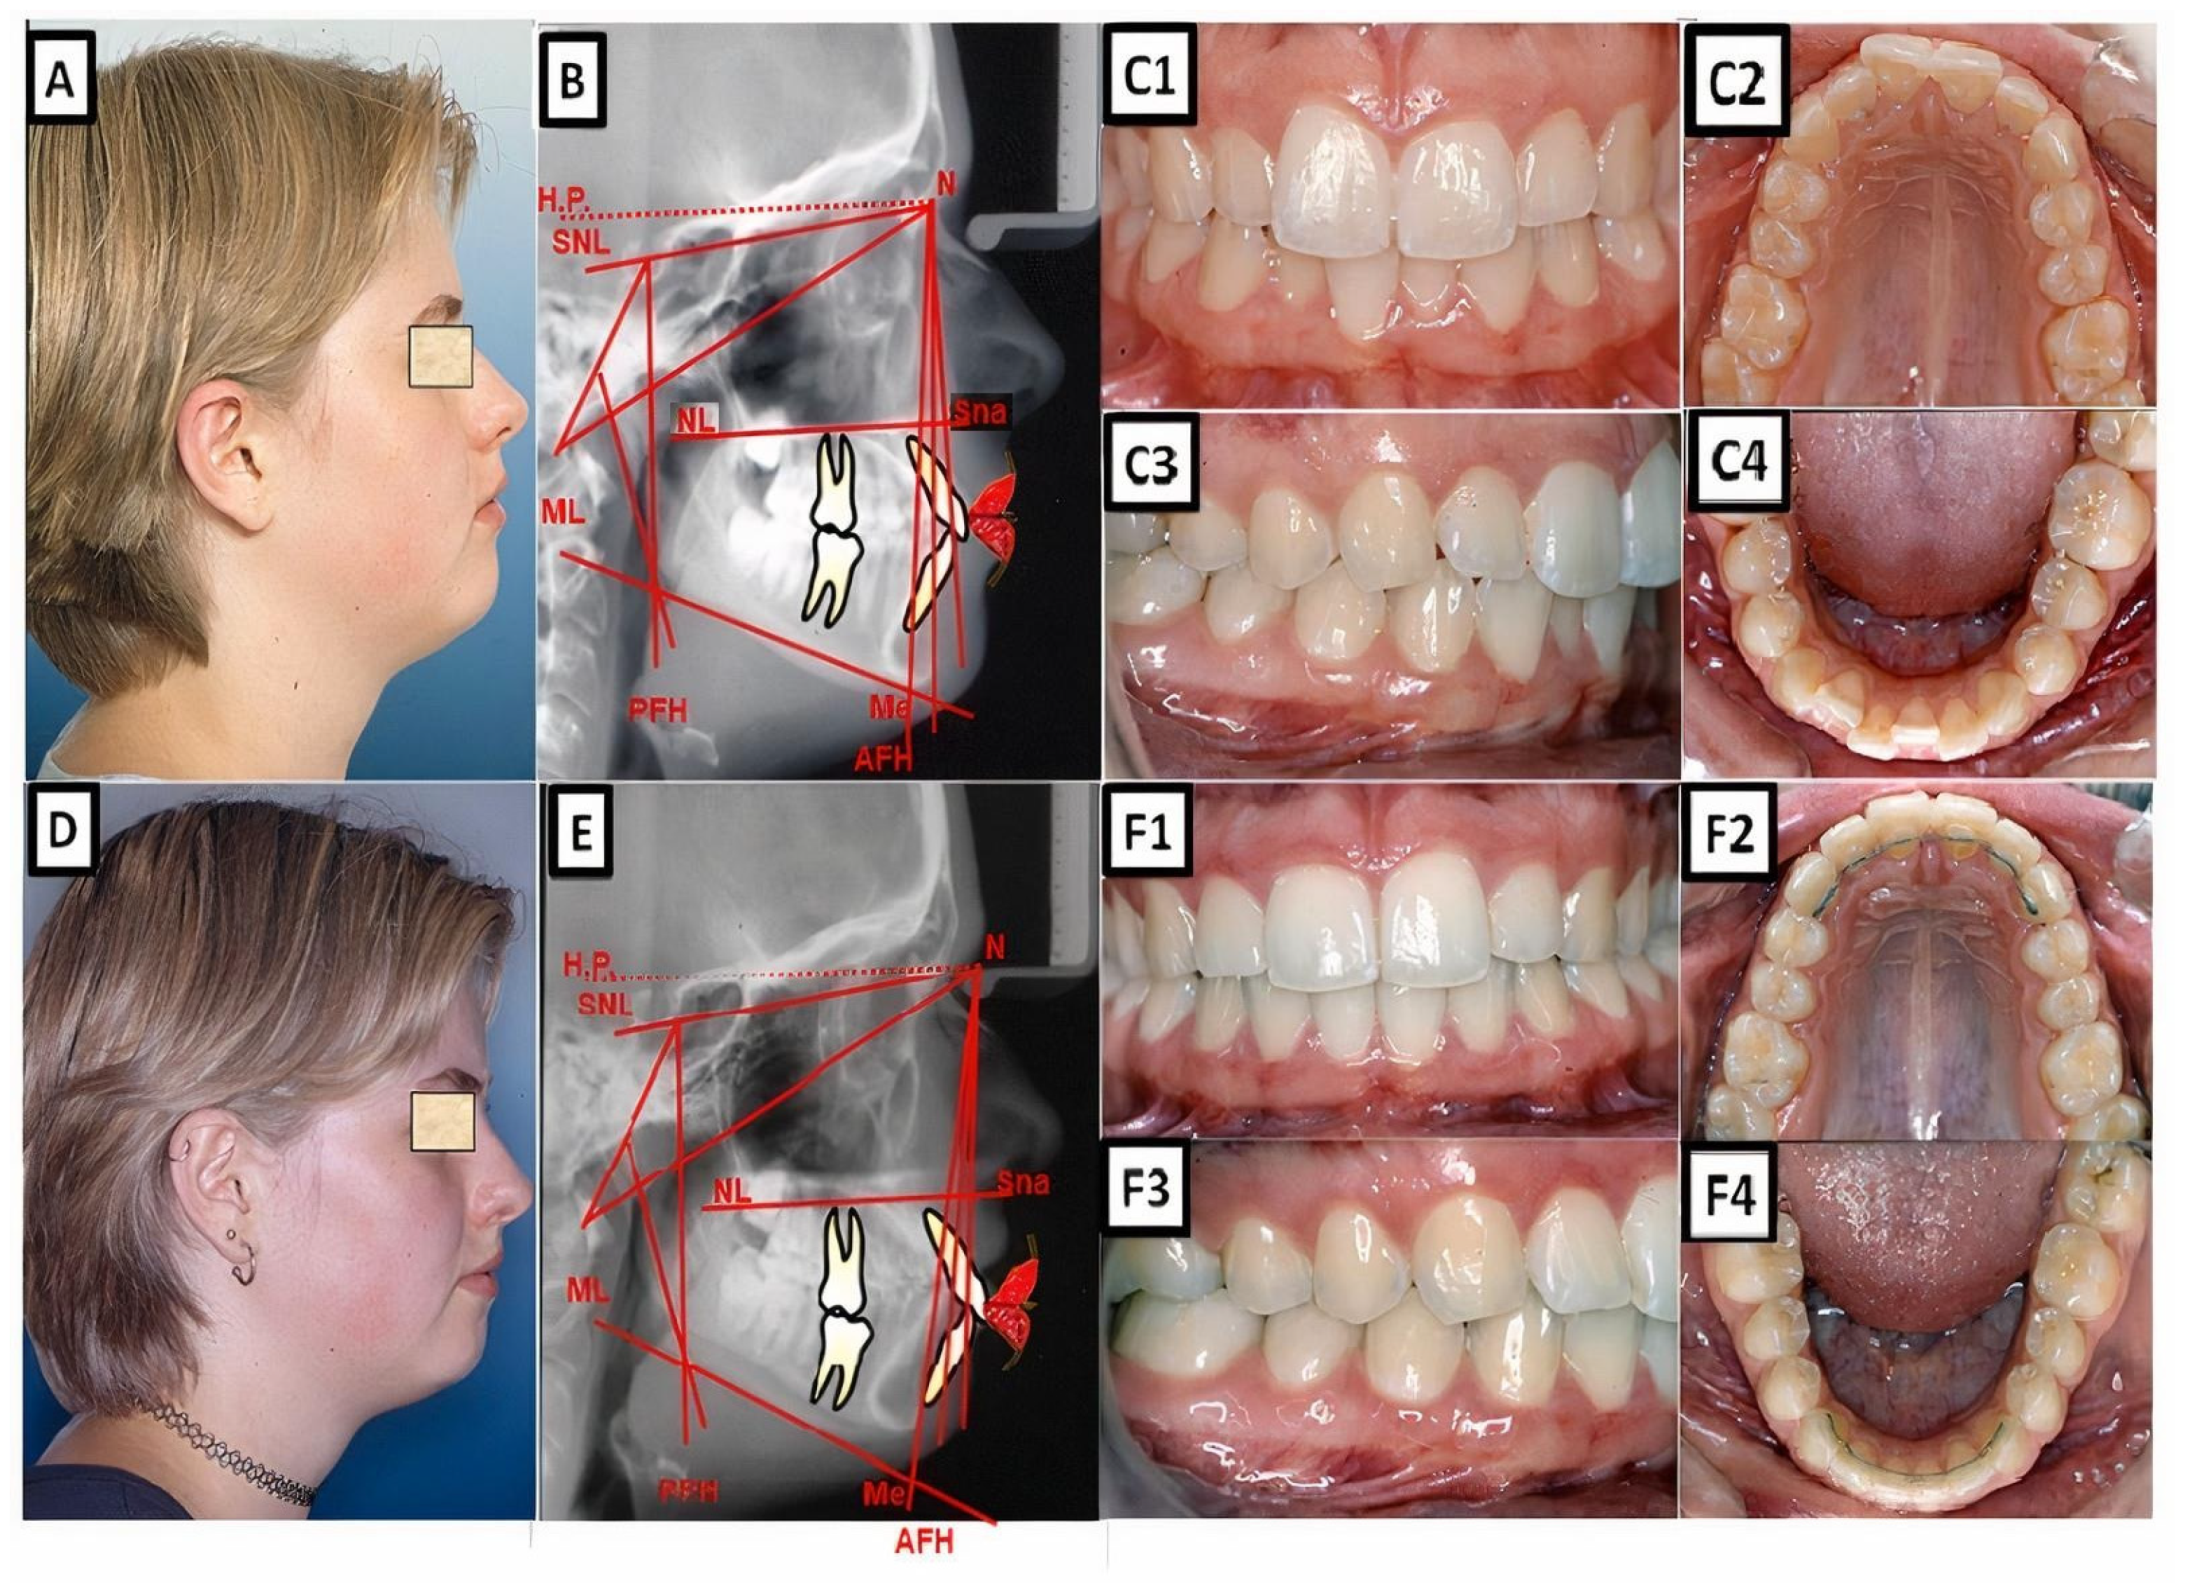

Figure 6.

A Abiometric photo and images of a patient with a Class I occlusion with other malpositions of the teeth in the three dimensions: transverse (lateral crossbite), sagittal (increased overjet), vertical (open bite), and crowding. The treatment was performed with a fixed appliance; the front teeth were extruded. (A–C) show before treatment, and (D–F) are after treatment.

Figure 7.

A biometric photo and images of a patient with a Class I occlusion with a dentoalveolar malposition of the teeth and crowding. The treatment was carried out with a fixed appliance. The space was created by approximal enamel reduction. (A–C) show before treatment, and (D–F) are after treatment.